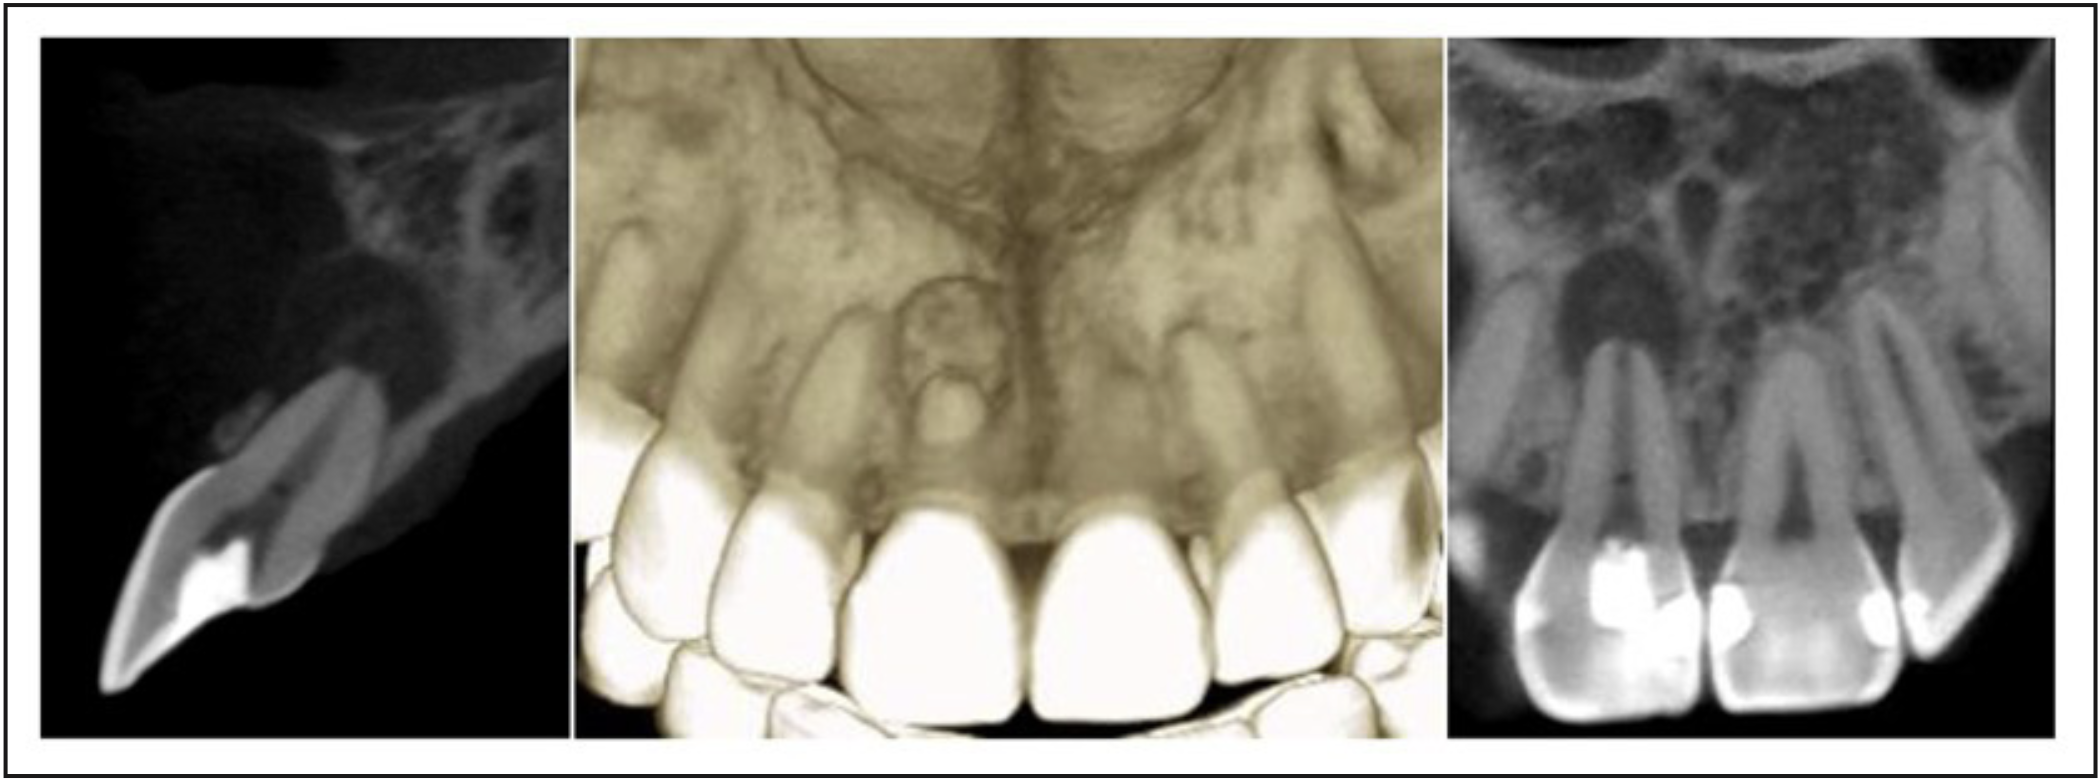

En el examen radiológico se observa una lesión osteolítica apical circunscrita de tamaño 5x8 mm. (Figura 1); además, se decidió complementar con tomografía computarizada de haz cónico debido a la movilidad presentada (Figura 2) en la que se logró visualizar la lesión en forma más precisa entregando una medida de aproximadamente 5x8,5x5mm, con compromiso de la tabla ósea vestibular, manteniendo una banda de tejido óseo a nivel cervical vestibular de entre 3,51 a 4,36 mm y mantención de la tabla palatina.

Figura 2. Tomografía computarizada de haz cónico del diente 1.1. Restauración coronaria penetrante. Canal radicular amplio con importantes signos de remodelado apical. Se observa lesión osteolítica periapical con límites netos, aparentemente corticalizada, cuyos diámetros mayores alcanzan 5,06x8,55x5,07mm. Adelgazamiento de la tabla vestibular. Trabeculado óseo heterogéneo.